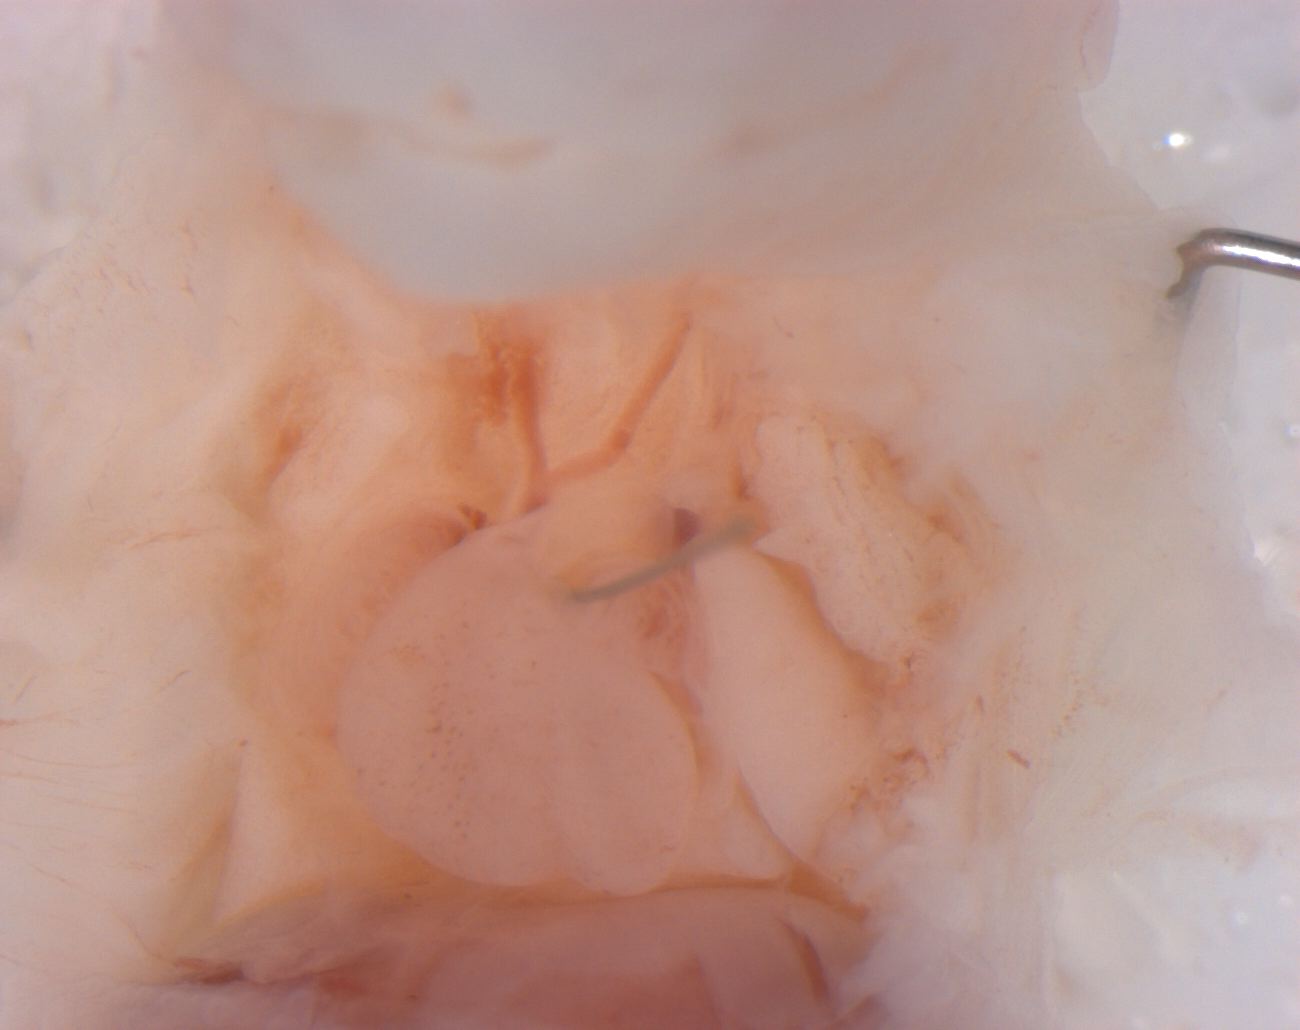

Caption Mutant 2289-004-2 (16.5) has hypoplastic aorta and double outlet right ventricle (DORV)

Copyright This image is from the Laboratory of Dr. Cecilia Lo, a member of the Cardiovascular Development Consortium (CvDC), Bench to Bassinet (B2B) program of the National Heart Lung and Blood Institute (NHLBI), and is displayed with the permission of the authors. J:175213